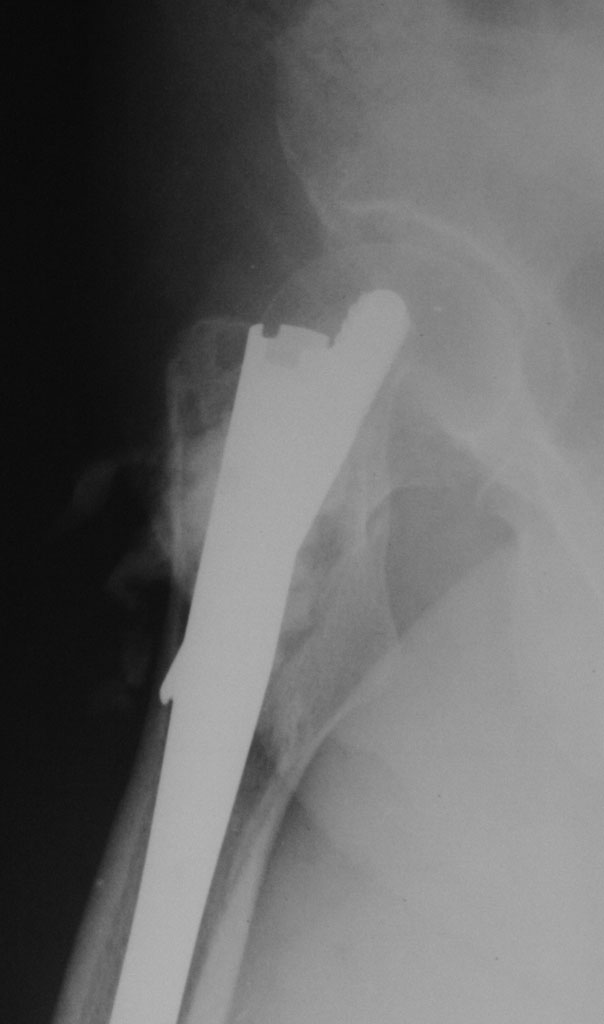

Добрый день. 2,5 месяца назад пациентке по поводу патологического чрезвертельного перелома правой бедренной кости (киста) был выполнена закрытая репозиция и БИОС гамма-гвоздем Stryker с заполнением полости Hydroset.

Гистологическое заключение: участки остеонекроза,хроническое воспаление. На этой неделе больная обратилась с жалобами на боли в области левого тазобедренного сустава. Со стороны оперированной ноги жалоб нет. Проведенное рентгенобследование выявило наличие полостного образования в проксимальном метадиафизе левой бедренной кости, перелом наружной стенки. Планируем выполнить БИОСлевой бедренной кости по методике аналогичной на правой ноге и этому случаю Какой фиксатор выбрать: длинную гамму или универсальный бедренный гвоздь?